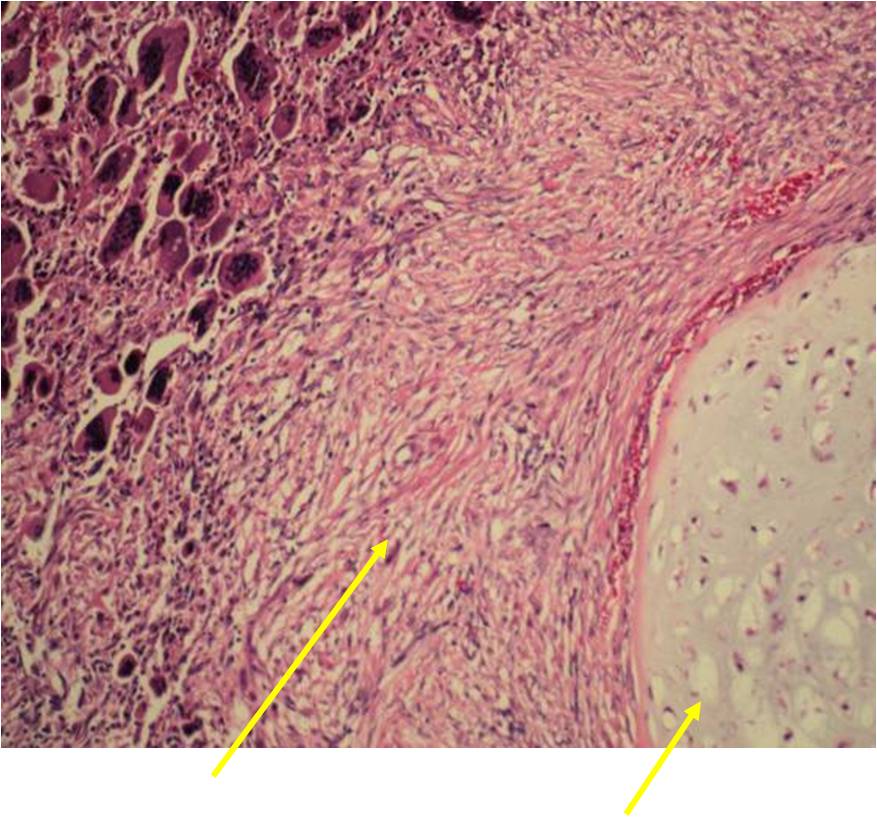

Junction of cartilaginous and noncartilaginous components is sharp and distinct. There are no dedifferentiated areas admixed in the middle of the cartilaginous areas

(Right Arrow) Spindle Cell Component

(Right Arrow) Low Grade Cartilage Component